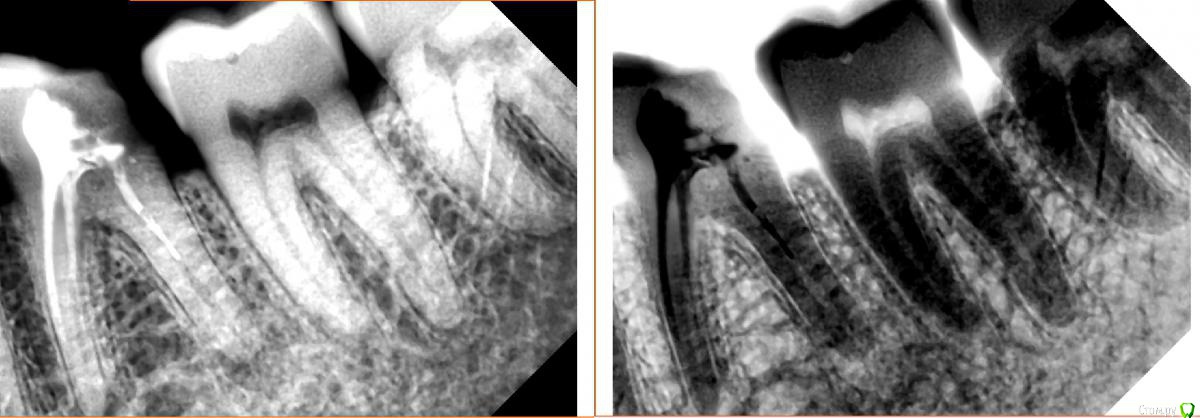

Витторио Орлионе Опубликовано 30 марта, 2017 Поделиться Опубликовано 30 марта, 2017 (изменено) Обратился пациент 1988 года рождения с жалобами на постоянные ноющие боли, усивиающиеся при накусывании на зуб беспокоящие его на протяжении 2х дней. Объективно зуб 3.7 ИНТАКТНЫЙ! ни пломб, ни кариеса не обнаружено, перкуссия его болезненная, температурная проба отрицательная, при накусывании на валик реагировал именно этот зуб. Поскольку зуб 3.6 стоял со старой пломбой и навиающими краями было решено пройтись ультразвуком, поскрести по сусекам слегка заполировать пломбу и оставить метрогил. На следующий день поднялась температура.Через день пришёл на приём. Зуб 3.7 сильно реагирует даже на слабое прикосновение.Не решился депульпировать, так как не вижу объективных причин для такого развития, откуда вообще периодонтит в интактном зубе?!? Пациент отправлен домой, так сказать под наблюдение.Верхние зубы также интактны, все антагонисты в наличии.Как быть и что делать? Изменено 30 марта, 2017 пользователем Витторио Орлионе 1 1 Ссылка на комментарий

DmitrySH Опубликовано 30 марта, 2017 Поделиться Опубликовано 30 марта, 2017 Объективно зуб 3.7 ИНТАКТНЫЙ! ни пломб, ни кариеса не обнаружено, перкуссия его болезненная, температурная проба отрицательная, при накусывании на валик реагировал именно этот зуб. А если внимательно посмотреть снимок, то на корне 37 нормальная такая кариозная полость Ссылка на комментарий

DmitrySH Опубликовано 31 марта, 2017 Поделиться Опубликовано 31 марта, 2017 (изменено) Полость не вижу На границе эмали и цемента корня нет кариеса? http://s010.radikal.ru/i311/1703/b9/fc60e3737466.jpg Изменено 31 марта, 2017 пользователем DmitrySH Ссылка на комментарий

Л Ю С Я Опубликовано 1 апреля, 2017 Поделиться Опубликовано 1 апреля, 2017 На границе эмали и цемента корня нет кариеса?Думаю это артефакт. Нужен визуальны осмотр, даже если и есть, то явно не до пульпы 1 Ссылка на комментарий

Жандос Муратович Опубликовано 1 апреля, 2017 Поделиться Опубликовано 1 апреля, 2017 На границе эмали и цемента корня нет кариеса? кариес есть однозначно,депульпируйте 7,зачем мучаете пациента. Ссылка на комментарий